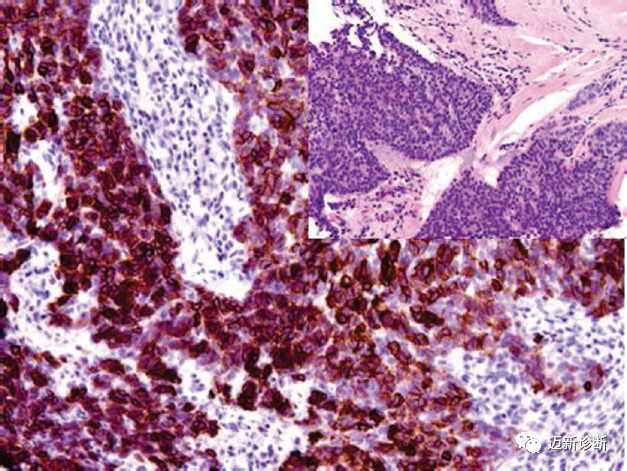

图1. AB型胸腺瘤,Pax-8在肿瘤性上皮细胞的细胞核阳性表达。

图2. 胸腺癌,Pax-8在恶性的胸腺上皮细胞核阳性表达。

图3. 胸腺癌,CD117在恶性的胸腺上皮中呈阳性表达。

图4. AB型胸腺瘤中,CK5/14在肿瘤性上皮细胞的胞质阳性表达。